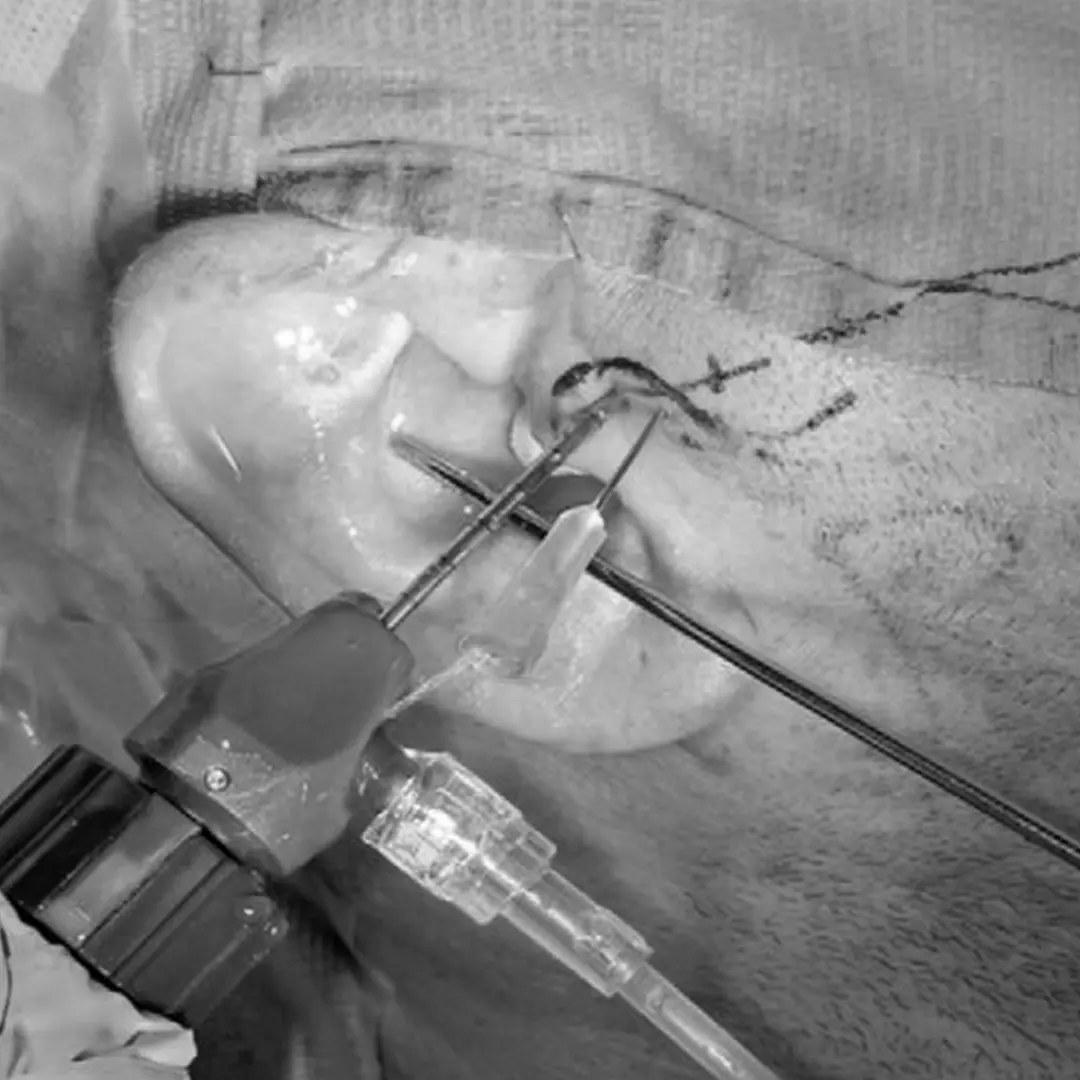

Tratamiento: Artrocentesis